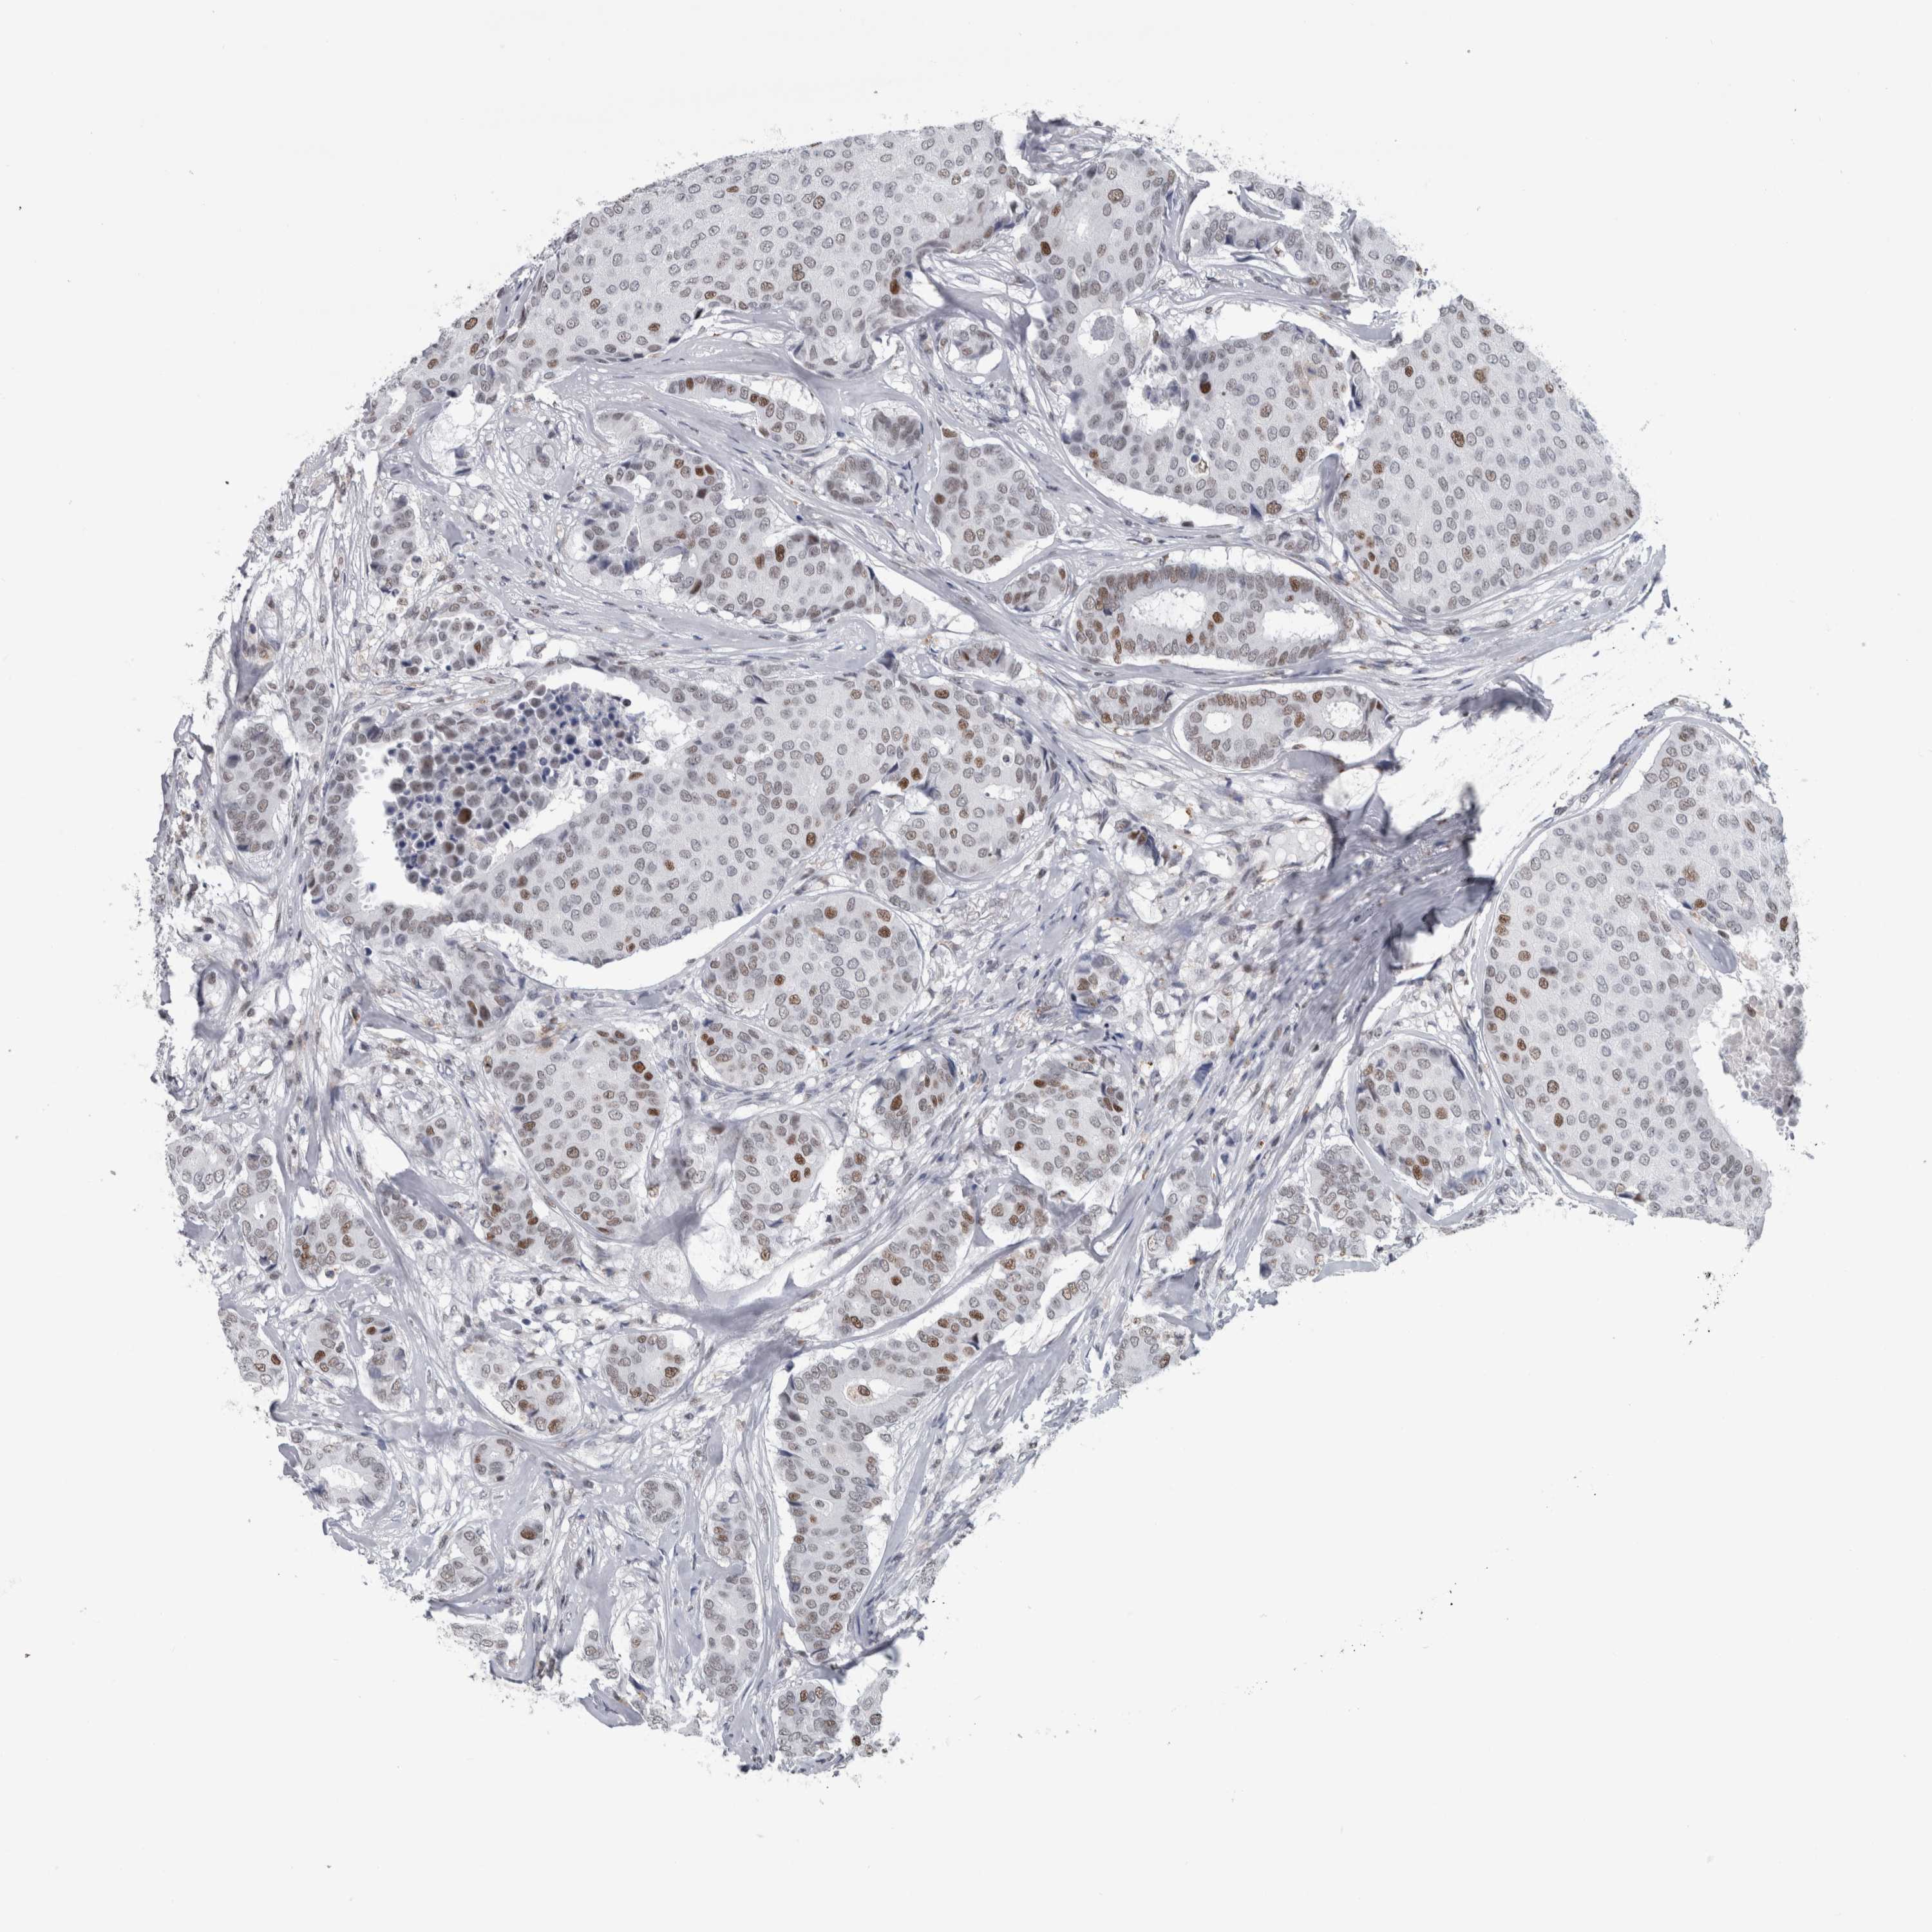

CANCER BREAST CANCER Show tissue menu

Breast cancer

Human cancer